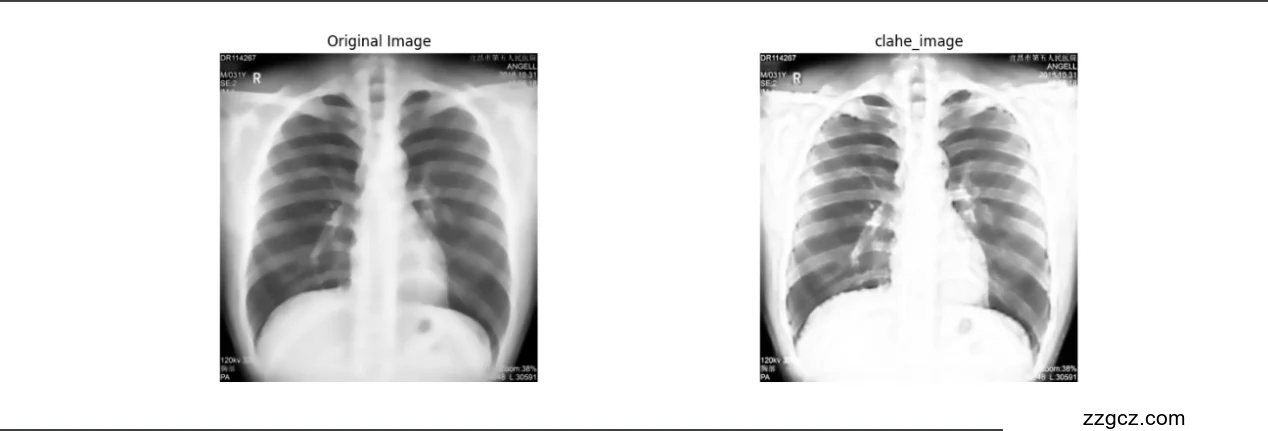

image_processor.show_results(preprocessed_image, clahe_image, './data/result/clahe_image.png', 'clahe_image')